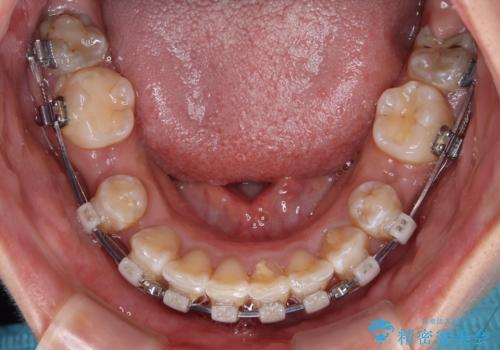

- 矯正装置

- 審美装置

- 2年3ヶ月

下顎は第二小臼歯を抜歯したため、治療期間が長期化すると思われましたが、大臼歯が後方に傾斜していたため、容易にスペースを閉じることができ、2年強で治療を終えることができました。